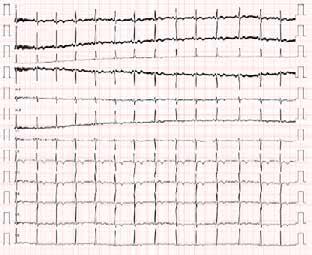

Issuu converts static files into: digital portfolios, online yearbooks, online catalogs, digital photo albums and more. Sign up and create your flipbook.